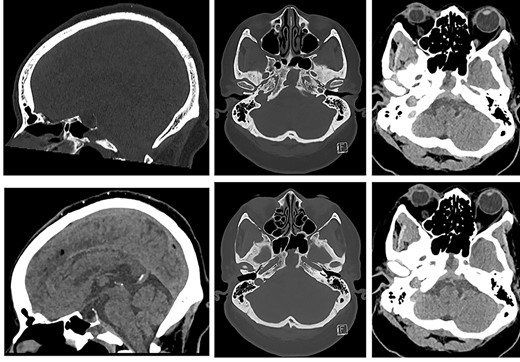

A CT head following her acute presentation showed no intracranial event (Fig. 4). There was minimal change in the size of the mucocele. Both anterior and posterior clival dehiscence had increased, reflecting remodelling or pressure deossification. The dehiscence was contiguous with a new smooth plaque of dural retroclival thickening that extended from the petrous ridge/dorsum sellae cranially to the basion caudally, features that are non-specific for extruded proteinaceous mucocele.

CT of the head (left: sagittal bone and soft tissue windows, and, right: axial bone window and soft tissue window at the same levels ×2) showing sphenoid mucopyocele, retroclival dural thickening and increasing clival dehiscence (anterior and posterior cortex).